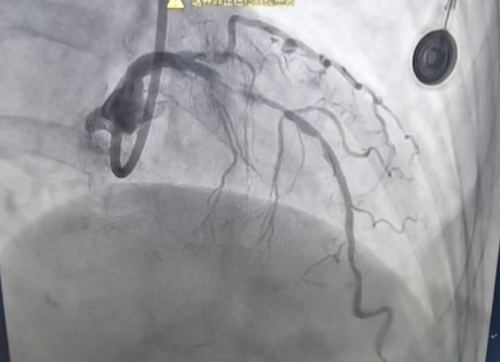

今年75岁的刘女士,2年前开始出现胸闷、气促、心前区闷胀感,未引起重视,近2月胸闷、气促较频繁才来就诊。为明确病因,行冠状动脉造影后,诊断为:冠状动脉粥样硬化性心脏病,三支血管病变,左前降支近中段弥漫性病变且360°严重钙化。

检查结果意味着患者的心脏冠状动脉出现了严重问题,左前降支全程弥漫性重度钙化、近中段狭窄,球囊通过困难,扩张极不充分,无法正常植入支架。

术中,叶国红副主任医师通过球囊低压扩张,向血管病变处发射非聚焦、低能量、脉冲式的冲击波,安全地碎裂浅、深层钙化,予前降支近中段植入支架1枚,术后造影见局部狭窄消失,支架膨胀完全,贴壁良好。